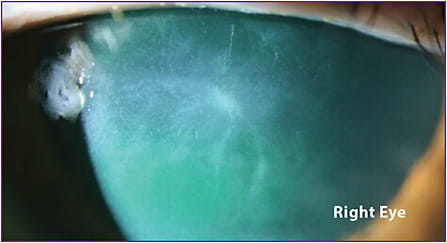

Figure 5 shows the patient’s right eye before treatment with cenegermin-bkbj. What appears to be an active dendrite is actually residual scarring within the corneal stroma due to a series of multiple episodes of recurrent keratitis through the years.